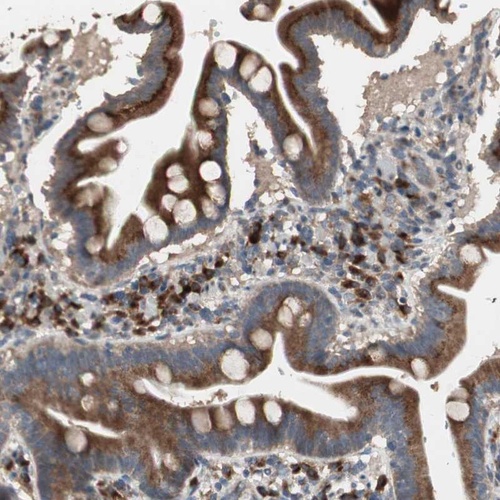

Immunohistochemical staining of human duodenum shows strong cytoplasmic positivity in glandular cells.